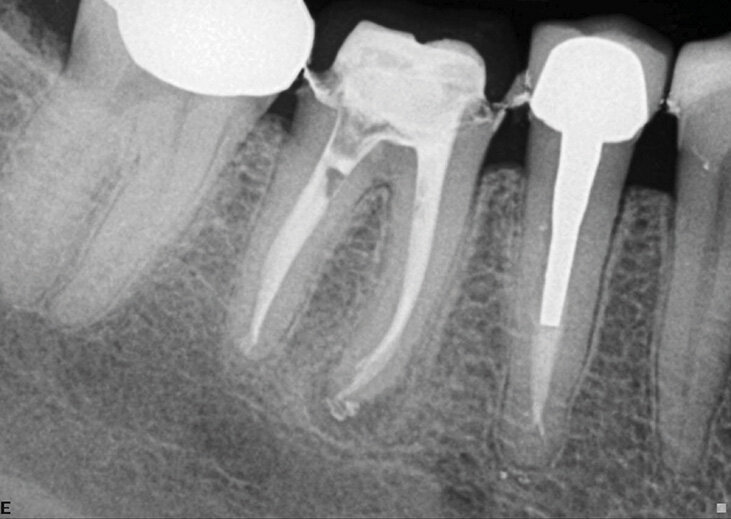

Slučaj 1 – Slika br. 2: Inicijalni periapikalni Rtg snimak

Slučaj 1 – Slika br. 3: Periapikalni kontrolni Rtg snimak nakon godinu dana od tretmana

Pacijent je upućen zbog nelagodnosti u donjim zubima koja je prerasla u pulsirajući bol. Nakon pregleda i rendgenskog snimanja, kod pacijenta je konstatovano da ima problema na prvom donjem molaru i premolaru. Prethodni kanal korena nije bio urađen na nivou standarda i izgleda kao obturacija sa jednim konusom (Slika br. 1). Pacijentu je predočen plan lečenja koji uključuje ponovno lečenje i premolara i molara i na kraju zamena obe krunice. Prošao sam kroz krunice za oba zuba u istoj sesiji. Kao što je ranije opisano, turpije koje sam koristio bile su Traverse 25 08 17 mm, a zatim se Zenflex 35-30-25 06 sužavaju do radne dužine. U ovom slučaju dodao sam konus 35 04 kao turpiju za proširenje na vrhu. Urađena je 3D obturacija pomoću elements IC za oba zuba. 12 meseci nakon tretmana pozvao sam pacijenta na kontrolu (Slika br. 2). Primetio sam da je zarastanje na oba zuba gotovo u potpunosti završeno, sa prelepom obturacijom sistema korenskih kanala i više izlaza. Krunica na molaru je zamenjena, ali na žalost krunica na premolaru nije, na snimku se vidi neka vrsta unutrašnjeg nakupljanja, te sam obavestio pacijenta da to može da ugrozi uspeh lečenja premolara.